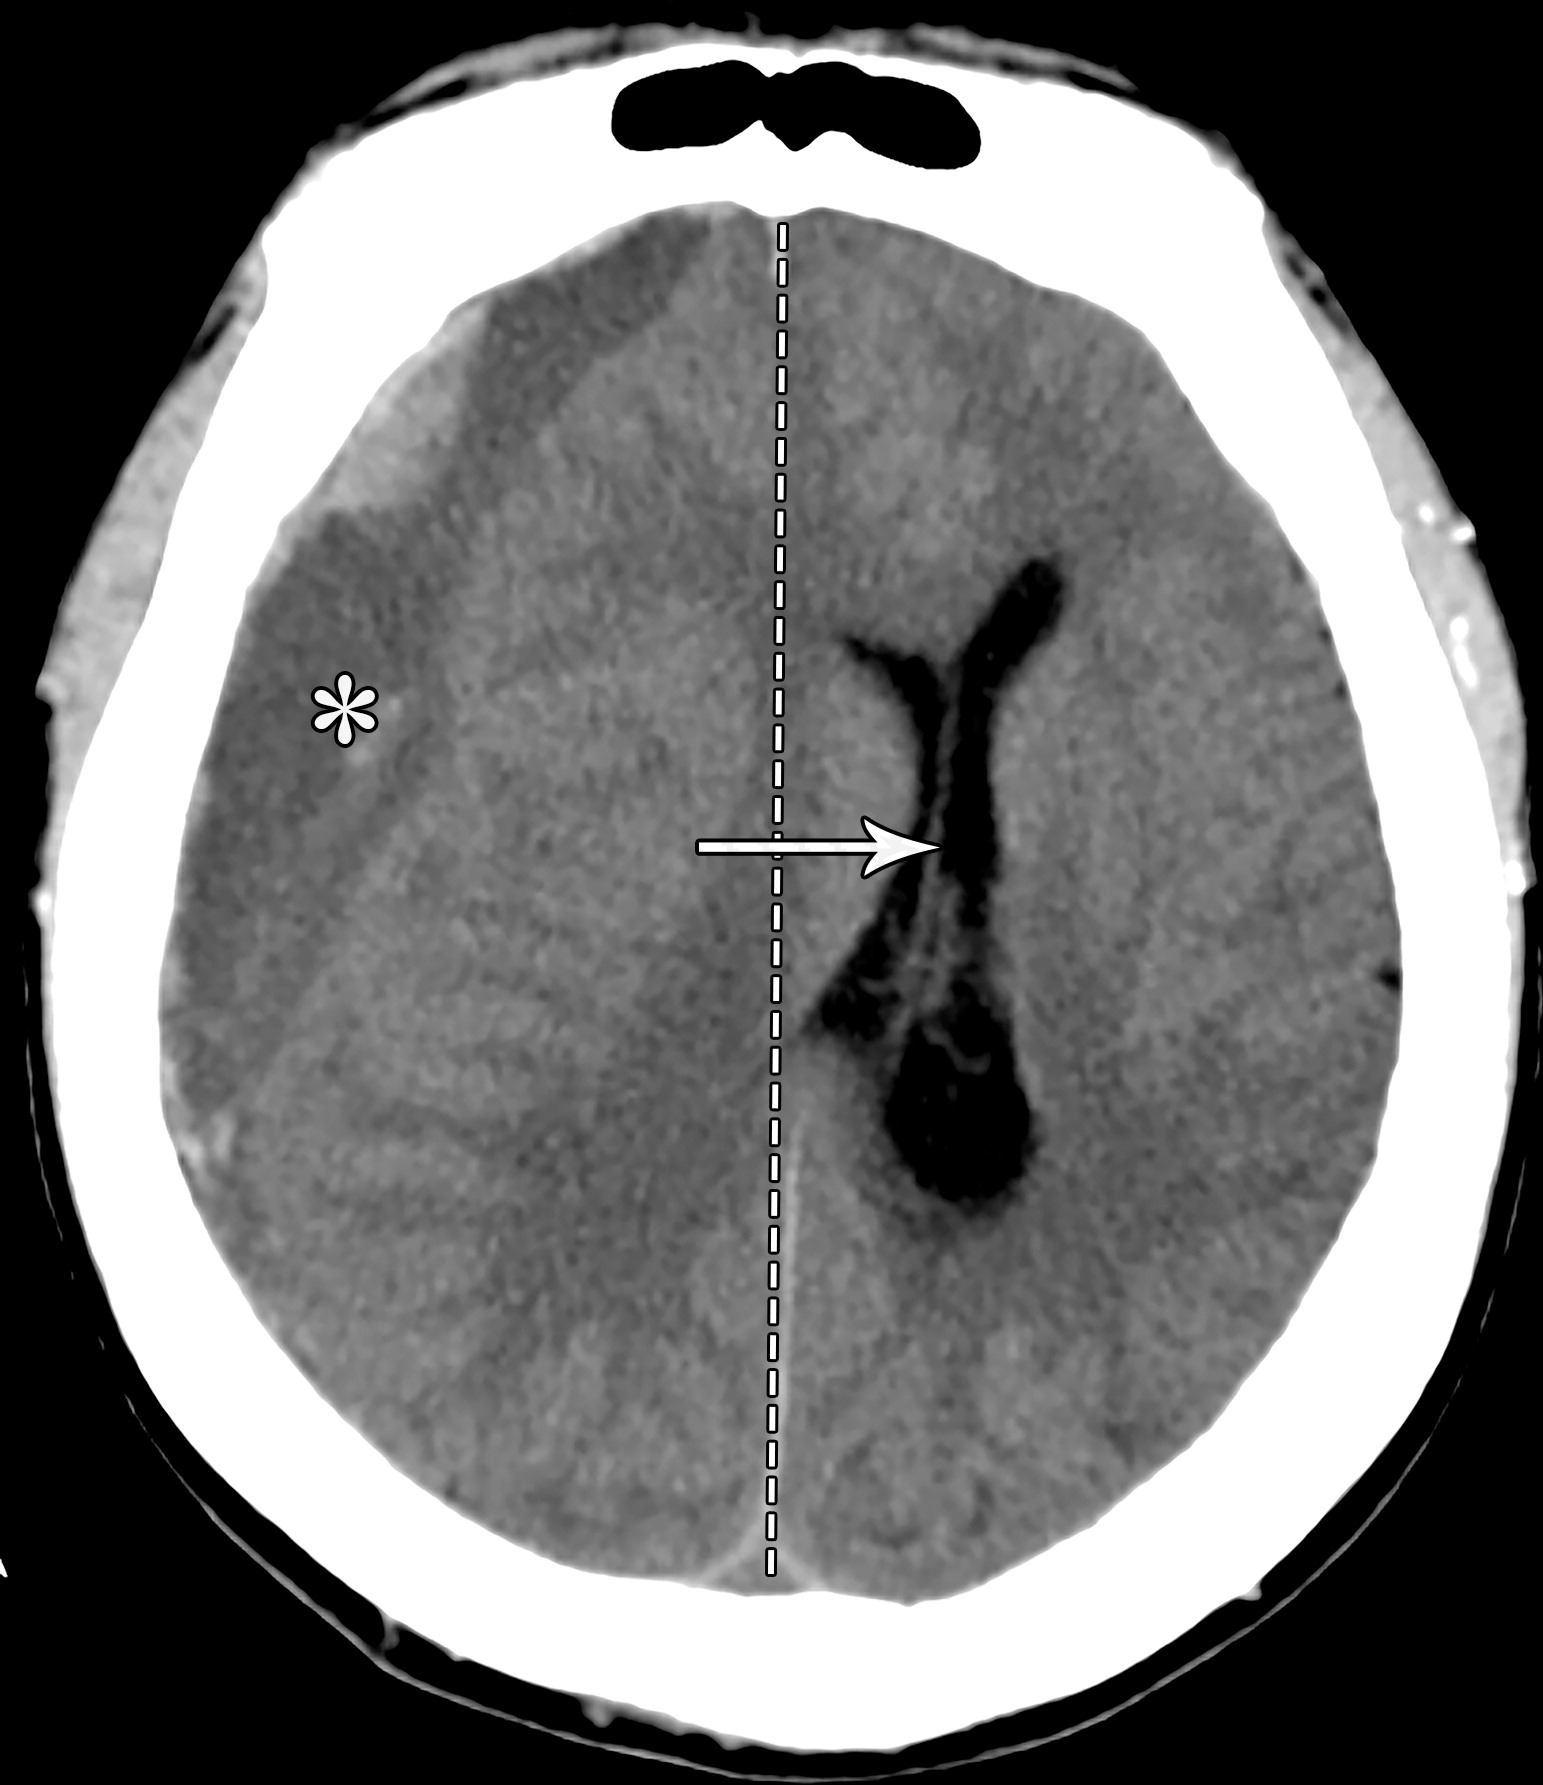

大脑镰下疝。平扫轴位CT示:右侧硬膜下血肿(*)伴混合密度影,表明处于不同时期的血液,血肿推挤使透明隔相对于中线(白色虚线)向左侧移位(白色长箭头)。右侧侧脑室受压,但是左侧侧脑室扩张。

e10b81f69aecfde7ed5f5612478dbcdc.jpeg

33岁男性,生殖细胞肿瘤脑转移患者的大脑镰下疝:冠状增强CT示大脑穹隆游离缘下方的扣带回从左向右疝入(白色弯箭头),并伴同侧胼胝体(*)的下侧移位,注意同侧脑室受压和对侧脑室的扩张(白色箭头)。

b970e936c5e18c5c1ffcf84ad6aaa810.jpeg

分房性硬膜下血肿及大脑镰下疝。左侧额叶挤压大脑镰(白色短箭头),以及蛛网膜下腔的消失。同时需要注意室间孔略向右侧移位(白色长箭头)。